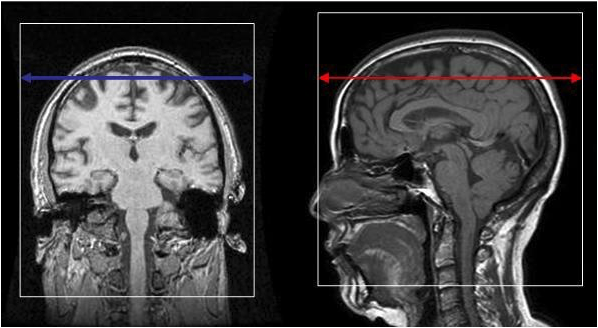

Axial FLAIR

Acquisition stack must fully cover subject's brain, starting at the vertex down to the cerebellum